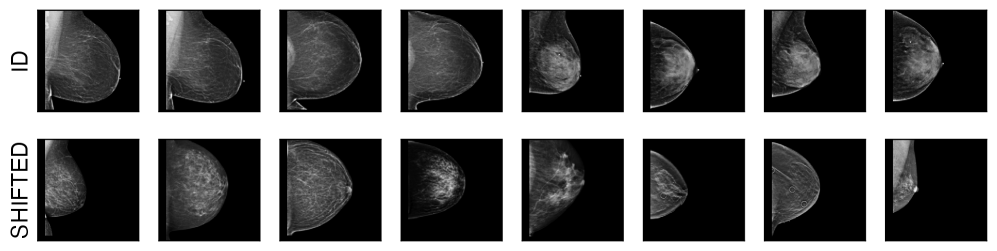

We analyse calibration robustness across different image classification tasks and real-world natural distribution shifts. First, we investigate robustness against geographic and sub-population shifts, in natural image classification using the Living17 and Entity30 datasets (Santurkar et al., 2020), as well as Wilds-iCam (Koh et al., 2021). Next, we analyse realistic shifts specific to medical imaging, a high-stakes domain where robustness and calibration are of particular importance. We study calibration robustness against: (i) scanner changes in breast density assessment models using the EMBED (Jeong et al., 2023) mammography dataset, (ii) scanner, population and prevalence changes in chest X-ray classification (No Finding / Diseased) using CheXpert (Irvin et al., 2019) and MIMIC-CXR (Johnson et al., 2019) (CXR), (iii) equipment, prevalence, and geographic location changes for diabetic retinopathy assessment models, combining multiple public fundus imaging datasets (Karthik & Sohier, 2019; Decencière et al., 2014; Dugas et al., 2015) (RETINA), and (iv) staining protocols changes in histopathology, using WILDS-CameLyon (Koh et al., 2021). Finally, we test against hard modality shifts in natural image classification using DomainNet (Peng et al., 2019) with ‘Real’ images as the ID domain. Details about datasets and ID/shifted domain definitions can be found in Appendix˜A.1, including visual examples of samples from both ID and shifted test sets for each dataset.

In this work we study realistic shifts in the medical imaging and natural images domain. For this we leverage multiple public datasets across various modalities and tasks. We here detail how we defined ID and OOD domains for non-standard benchmark datasets. We summarise splits and ID/shifted domains definitions in Table˜A.1. In Figs.˜A.1 and A.2 we illustrate the types of shift by showing examples of images from both the ID and the shifted sets for each dataset.

EMBED

we analyse robustness against scanner changes for breast density assessment models in mammography. For this purpose, we use the public available EMBED dataset (Jeong et al., 2023). This dataset contains data from 6 different scanners (Selenia Dimensions, Senographe Essential, Senograph 2000D, Lorad Selenia, Clearview CSm, Senographe Pristina). In this work, we used Selenia Dimensions (2D images) as the ID scanner for training and validation, and all the other scanners, as well as the C-view images from Selenia Dimensions, are used as shifted test sets, resulting in six shifted test sets.